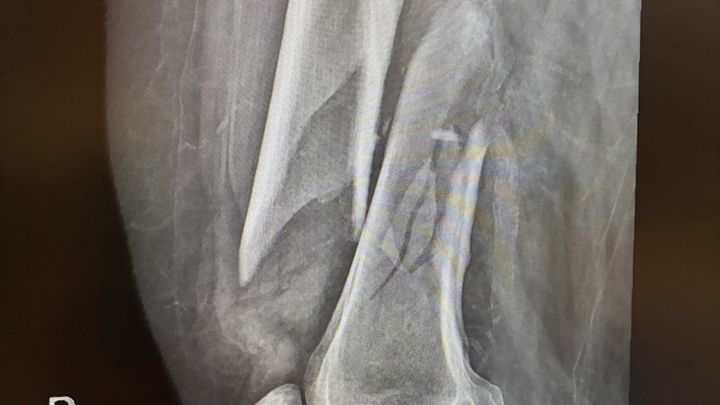

In mid October of 2025 I fell and broke my right femur and had to have surgery to place a metal rod and screws in my leg. I have been in physical rehabilitation since my surgery. The recovery period for a broken femur is long and I have made significant progress however I still can not walk. I exhausted my Medicare days available for rehabilitation and I'm in danger of being sent home unable to walk. I'm right on the verge of walking again but I need to raise money to pay out of pocket for my remaining therapy needs. The cost is $270 a day and I need about 3 more weeks in therapy. I'm trying to raise $6,000 to cover these expenses. Anything you're able to give will be greatly appreciated. Thank you.